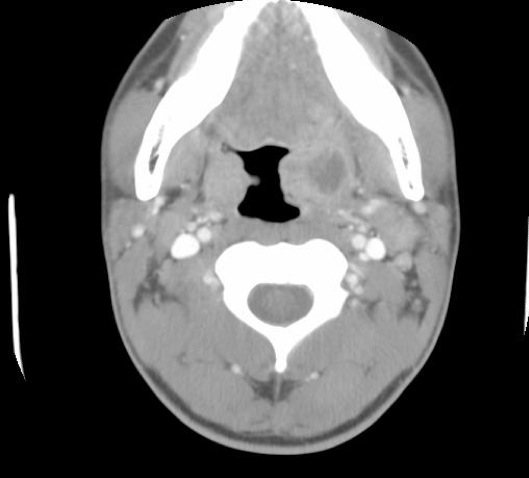

В некоторых случаях может потребоваться инструментальное обследование – УЗИ, КТ, рентгенография. Это необходимо для исключения развития новообразований и определения точной локализации воспалительного процесса.

Прежде чем поставить диагноз «паратонзиллярный абсцесс», необходимо провести дифференциальную диагностику со скарлатиной, дифтерией, злокачественными опухолями и аневризмой сонной артерии.